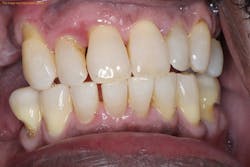

Periodontal desiccation offers many benefits to the patient and clinician. The process of periodontal desiccation works by drying out the plaque biofilm and the necrotic tissue that could remain after periodontal scaling and root planing.2 Once the biofilm matrix is dry, it can no longer remain attached to the tooth’s surface, so it is flushed out of the periodontal pocket. This benefits the patient by reducing the high counts of microorganisms in this localized area.2

Another benefit of periodontal desiccation is that the biofilm cannot grow and divide when desiccated, thus there is a high likelihood that the periodontal bacteria are completely erased in the pocket.2,3